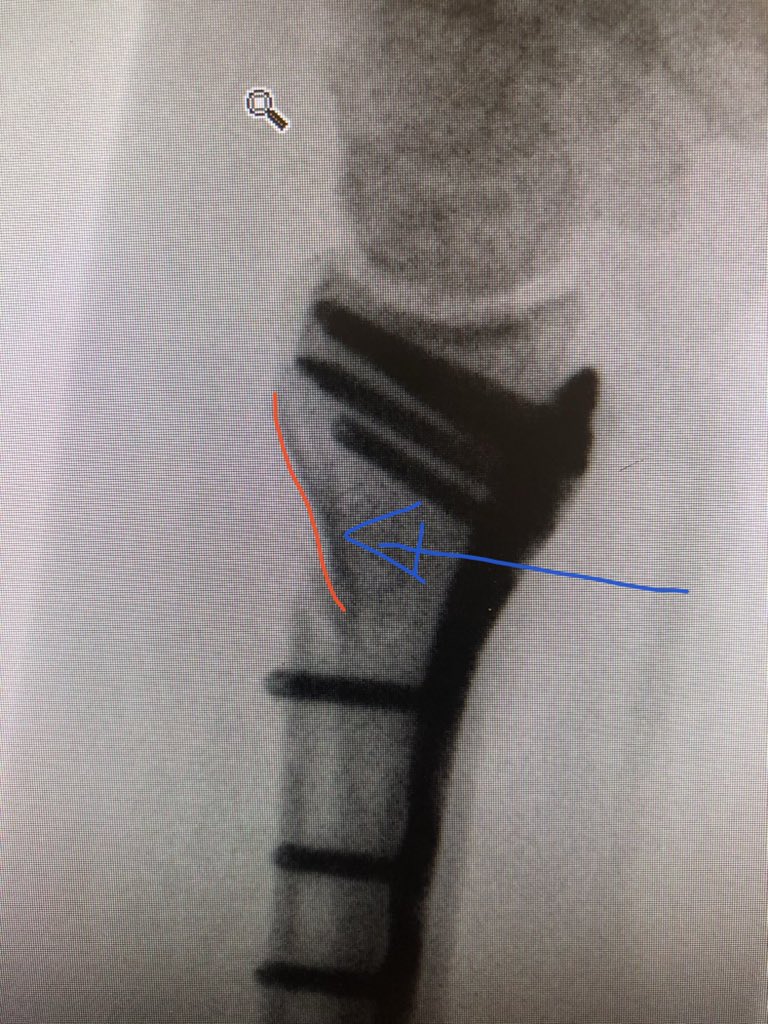

Point 2:

The dorsal metaphyseal comminution. The dorsal cortex fragment is ‘fallen in’ inside the osteoporotic metaphyseal void.

I addressed this after plating finished, made a 4.5 mm drill hole in the ‘window’ of the plate to push the fragment and fill in graft substitute.

This was the patient at 2 weeks. Already on range of motion. The flat lateral X-ray always looks like the screws are in the joint. That’s because of the distal radius joint inclination angle.

Take intra-operative 20 degree elevated lateral shot to see through the joint.